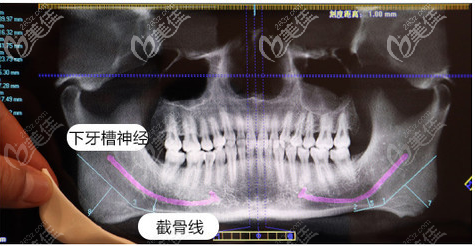

做磨骨手術(shù)前醫(yī)院會進行數(shù)字化設(shè)計,怎么截,截骨截多少,醫(yī)生都會在設(shè)計后為我詳細講解。

找高俊明做下頜角術(shù)前拍ct這是護士小姐姐給我拍的高俊明磨骨手術(shù)過程圖。